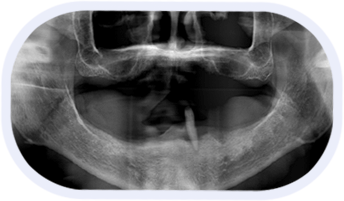

“穿颧种植”是一种通过颧骨固定种植牙的技术,将种植体植入到位于人面中部前,眼眶的外下方呈菱形较硬的骨头——颧骨,是当今难度很大的种植技术,被种植牙界誉为“珠穆朗玛峰”的顶级技术,俗称“无土栽培术”。一般重度颌骨吸收患者需要2颗穿颧种植体就可以获得很好的固位效果,在前牙区可以垂直植入2至3颗普通种植体。对于较度严重的颌骨吸收的患者,还可以使用四颗穿颧种植体。

穿颧种植技术在术前需要在计算机上进行手术模拟,在3D数字化导板辅助下,精准手术。手术室内空气清新、爽洁,环境舒适,可以防止外来污染物的进入,极大地降低了感染率,很大程度上保证穿颧种植手术的安全性。